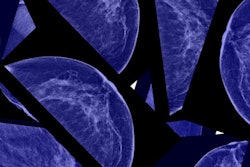

Assessing the risk of breast cancer in five-year increments in women with dense breast tissue is a more effective way to determine the need for supplemental imaging than scanning all women with dense tissue, according to a study published online July 1 in JAMA Internal Medicine.

Current notification laws mandate that screening mammography reports to physicians and women include breast density information and that women with dense tissue be encouraged to undergo additional imaging. But according to the researchers, this all-encompassing approach may be too broad.

"Instead of discussing supplemental imaging with all women with dense breasts, it may be more efficient to identify women at high risk of advanced breast cancer who may benefit most from supplemental imaging," the team wrote.

Women with dense breast tissue accounted for 47% of the study cohort, and 60% of these had advanced cancers. Kerlikowske's group also found the following:

- Low rates of advanced breast cancer occurred in 34.5% of screened women with dense breasts.

- High rates of advanced breast cancer occurred in women with heterogeneously dense breasts and a five-year risk of 2.5% or higher (6% of screened women).

- High rates of advanced breast cancer occurred in women with extremely dense breasts and a five-year risk of 1% or higher (6.5% of screened women).

- Women at high advanced cancer risk made up 12.5% of all who were screened and had 27.1% of advanced cancers.

The results suggest that density notification should be combined with measured breast cancer risk, so women at highest risk for advanced cancer are targeted for supplemental imaging discussions and women at low risk are not, Kerlikowske's group concluded.

"BI-RADS breast density combined with BCSC five-year risk may offer a more efficient strategy for supplemental imaging discussions than targeting all women with dense breasts," the team wrote.